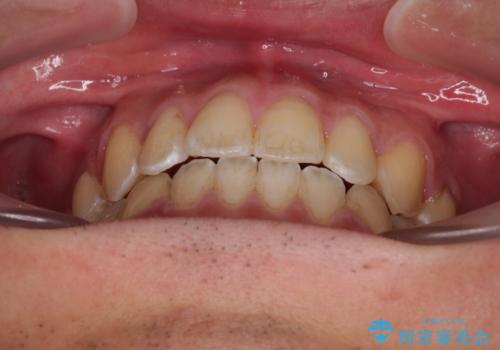

ワイヤー矯正を併用したインビザライン矯正治療

- 前歯のデコボコを気にして来院された患者様です。

歯列としてはワイヤー装置でもインビザラインでも対応可能でしたが、インビザラインが苦手とする上顎側切歯(真ん中から2番目の歯)の舌側転位が顕著でした。

治療の確実性を上げるために、インビザライン開始前に上顎のワイヤー装置にて舌側転位を解消し、その後インビザラインにて矯正治療を行うこととしました。

前歯のデコボコが早めに改善され、スムーズに治療を終えることができました。